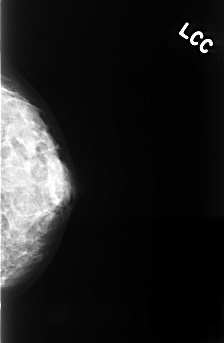

| ics_version 1.0 filename C-0336-1 DATE_OF_STUDY 22 3 1996 PATIENT_AGE 35 FILM FILM_TYPE REGULAR DENSITY 3 DATE_DIGITIZED 12 10 1998 DIGITIZER LUMISYS LASER SEQUENCE LEFT_CC LINES 4448 PIXELS_PER_LINE 2912 BITS_PER_PIXEL 12 RESOLUTION 50 NON_OVERLAY LEFT_MLO LINES 4528 PIXELS_PER_LINE 2920 BITS_PER_PIXEL 12 RESOLUTION 50 NON_OVERLAY RIGHT_CC LINES 4488 PIXELS_PER_LINE 2888 BITS_PER_PIXEL 12 RESOLUTION 50 OVERLAY RIGHT_MLO LINES 4528 PIXELS_PER_LINE 2912 BITS_PER_PIXEL 12 RESOLUTION 50 OVERLAY |

| FILE: C_0336_1.RIGHT_CC.OVERLAY TOTAL_ABNORMALITIES 1 ABNORMALITY 1 LESION_TYPE MASS SHAPE OVAL MARGINS CIRCUMSCRIBED ASSESSMENT 4 SUBTLETY 5 PATHOLOGY BENIGN TOTAL_OUTLINES 1 BOUNDARY |